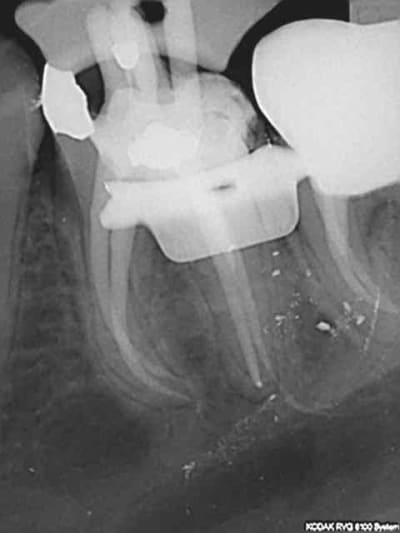

4eme sur 13, endo classique monocone puis tenon réalisé au machtou chauffé ca a du bon la condensation verticale à chaud !) je suputais un canal latéral vu l'image de départ radioclaire latéro radiculaire.

as tu recherché un deuxième canal parce que à la radio initiale on dirait qu'il y a deux apex sur cette dent???

Ah les canuax latéraux, ça fait toujours plaisir de les obturer !!!